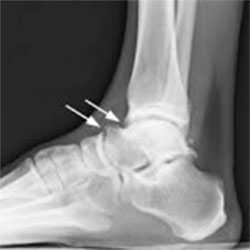

Пациенту обязательно назначают рентгенограмму. На рентгенологическом снимке доктор легко увидит остеофиты - костные разрастания, появившиеся из-за воспалительного процесса. Дополнительно выполняется снимок в стрессовом положении. На нем доктор определит, есть ли соударение костей.

- I степень - характеризуется наличием шпоры размером до 3 мм на большеберцовой кости, носит название синовиальной степени;

- II степень - остеохондральная, размер шпоры превышает отметку в 3 мм;

- III степень - можно определить экзостозы с фрагментацией или без нее, шпора появляется также на таранной кости;

- IV степень - развиваются изменения, характеризующие артрозы.